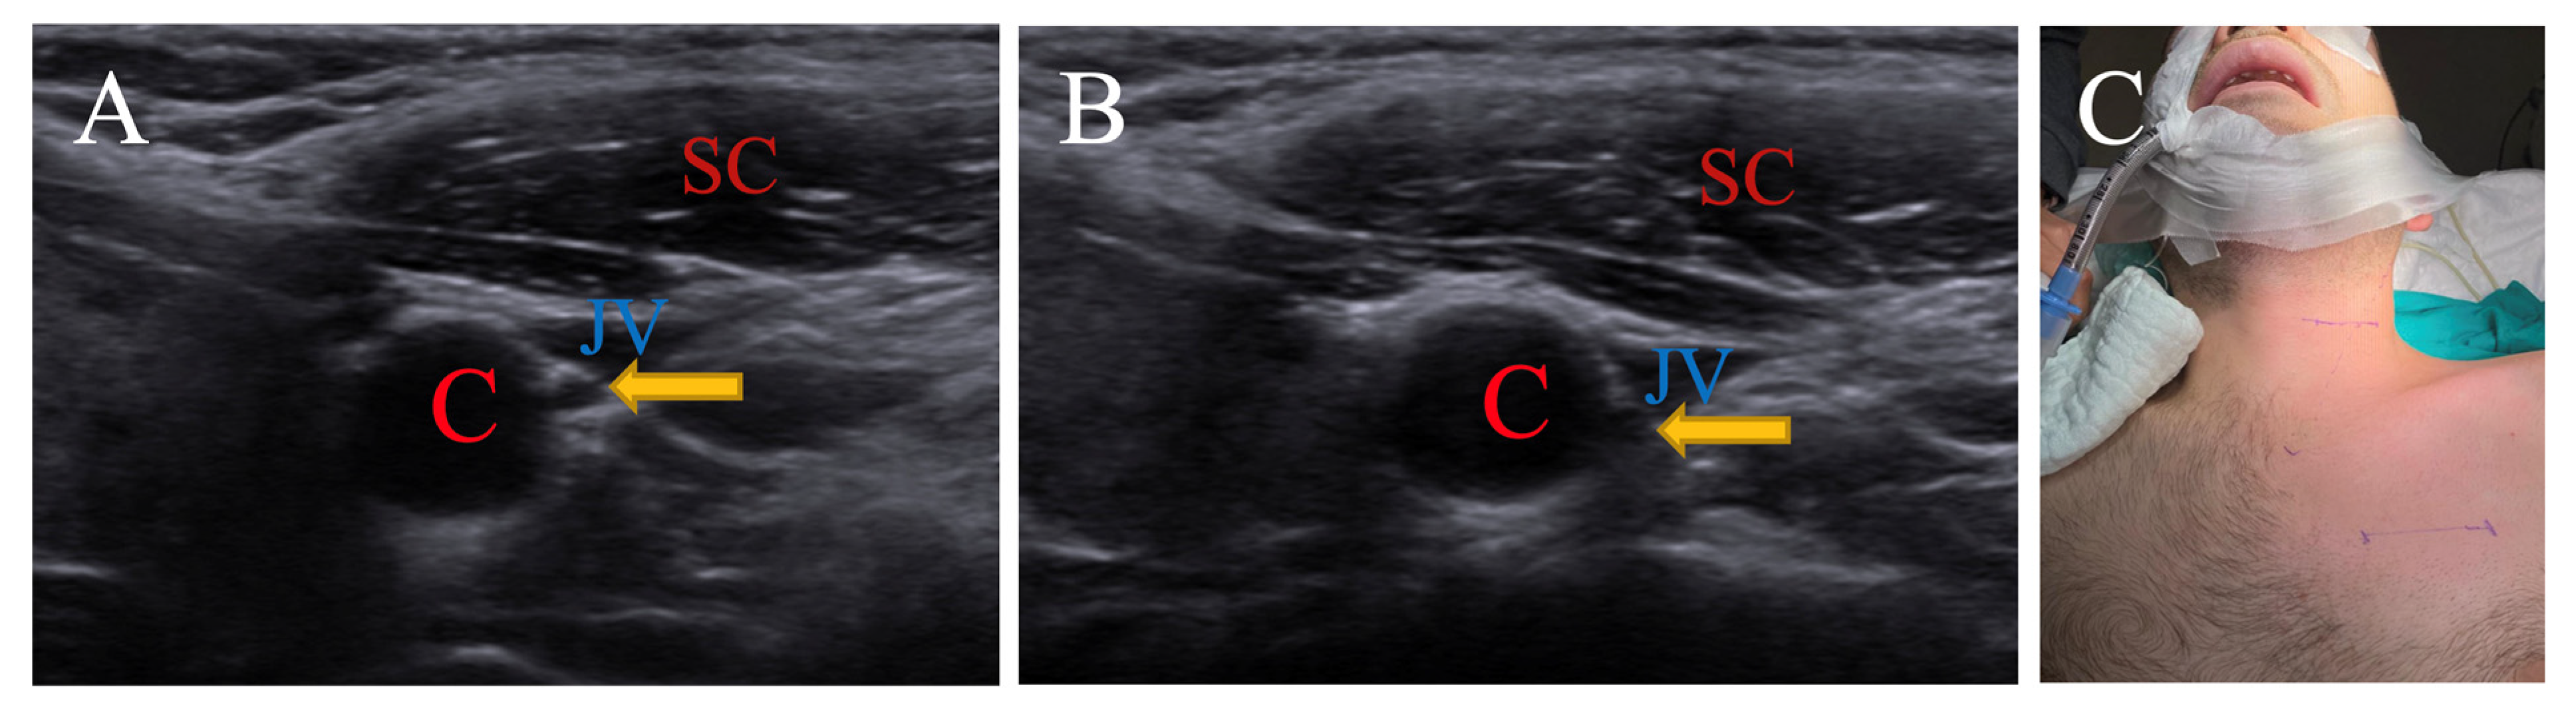

3.1.3. Neutral Position for Nervus Vagus

| SCM | Sternocleidomastoid |

| C | Carotid artery |

| JV | Jugular vein |